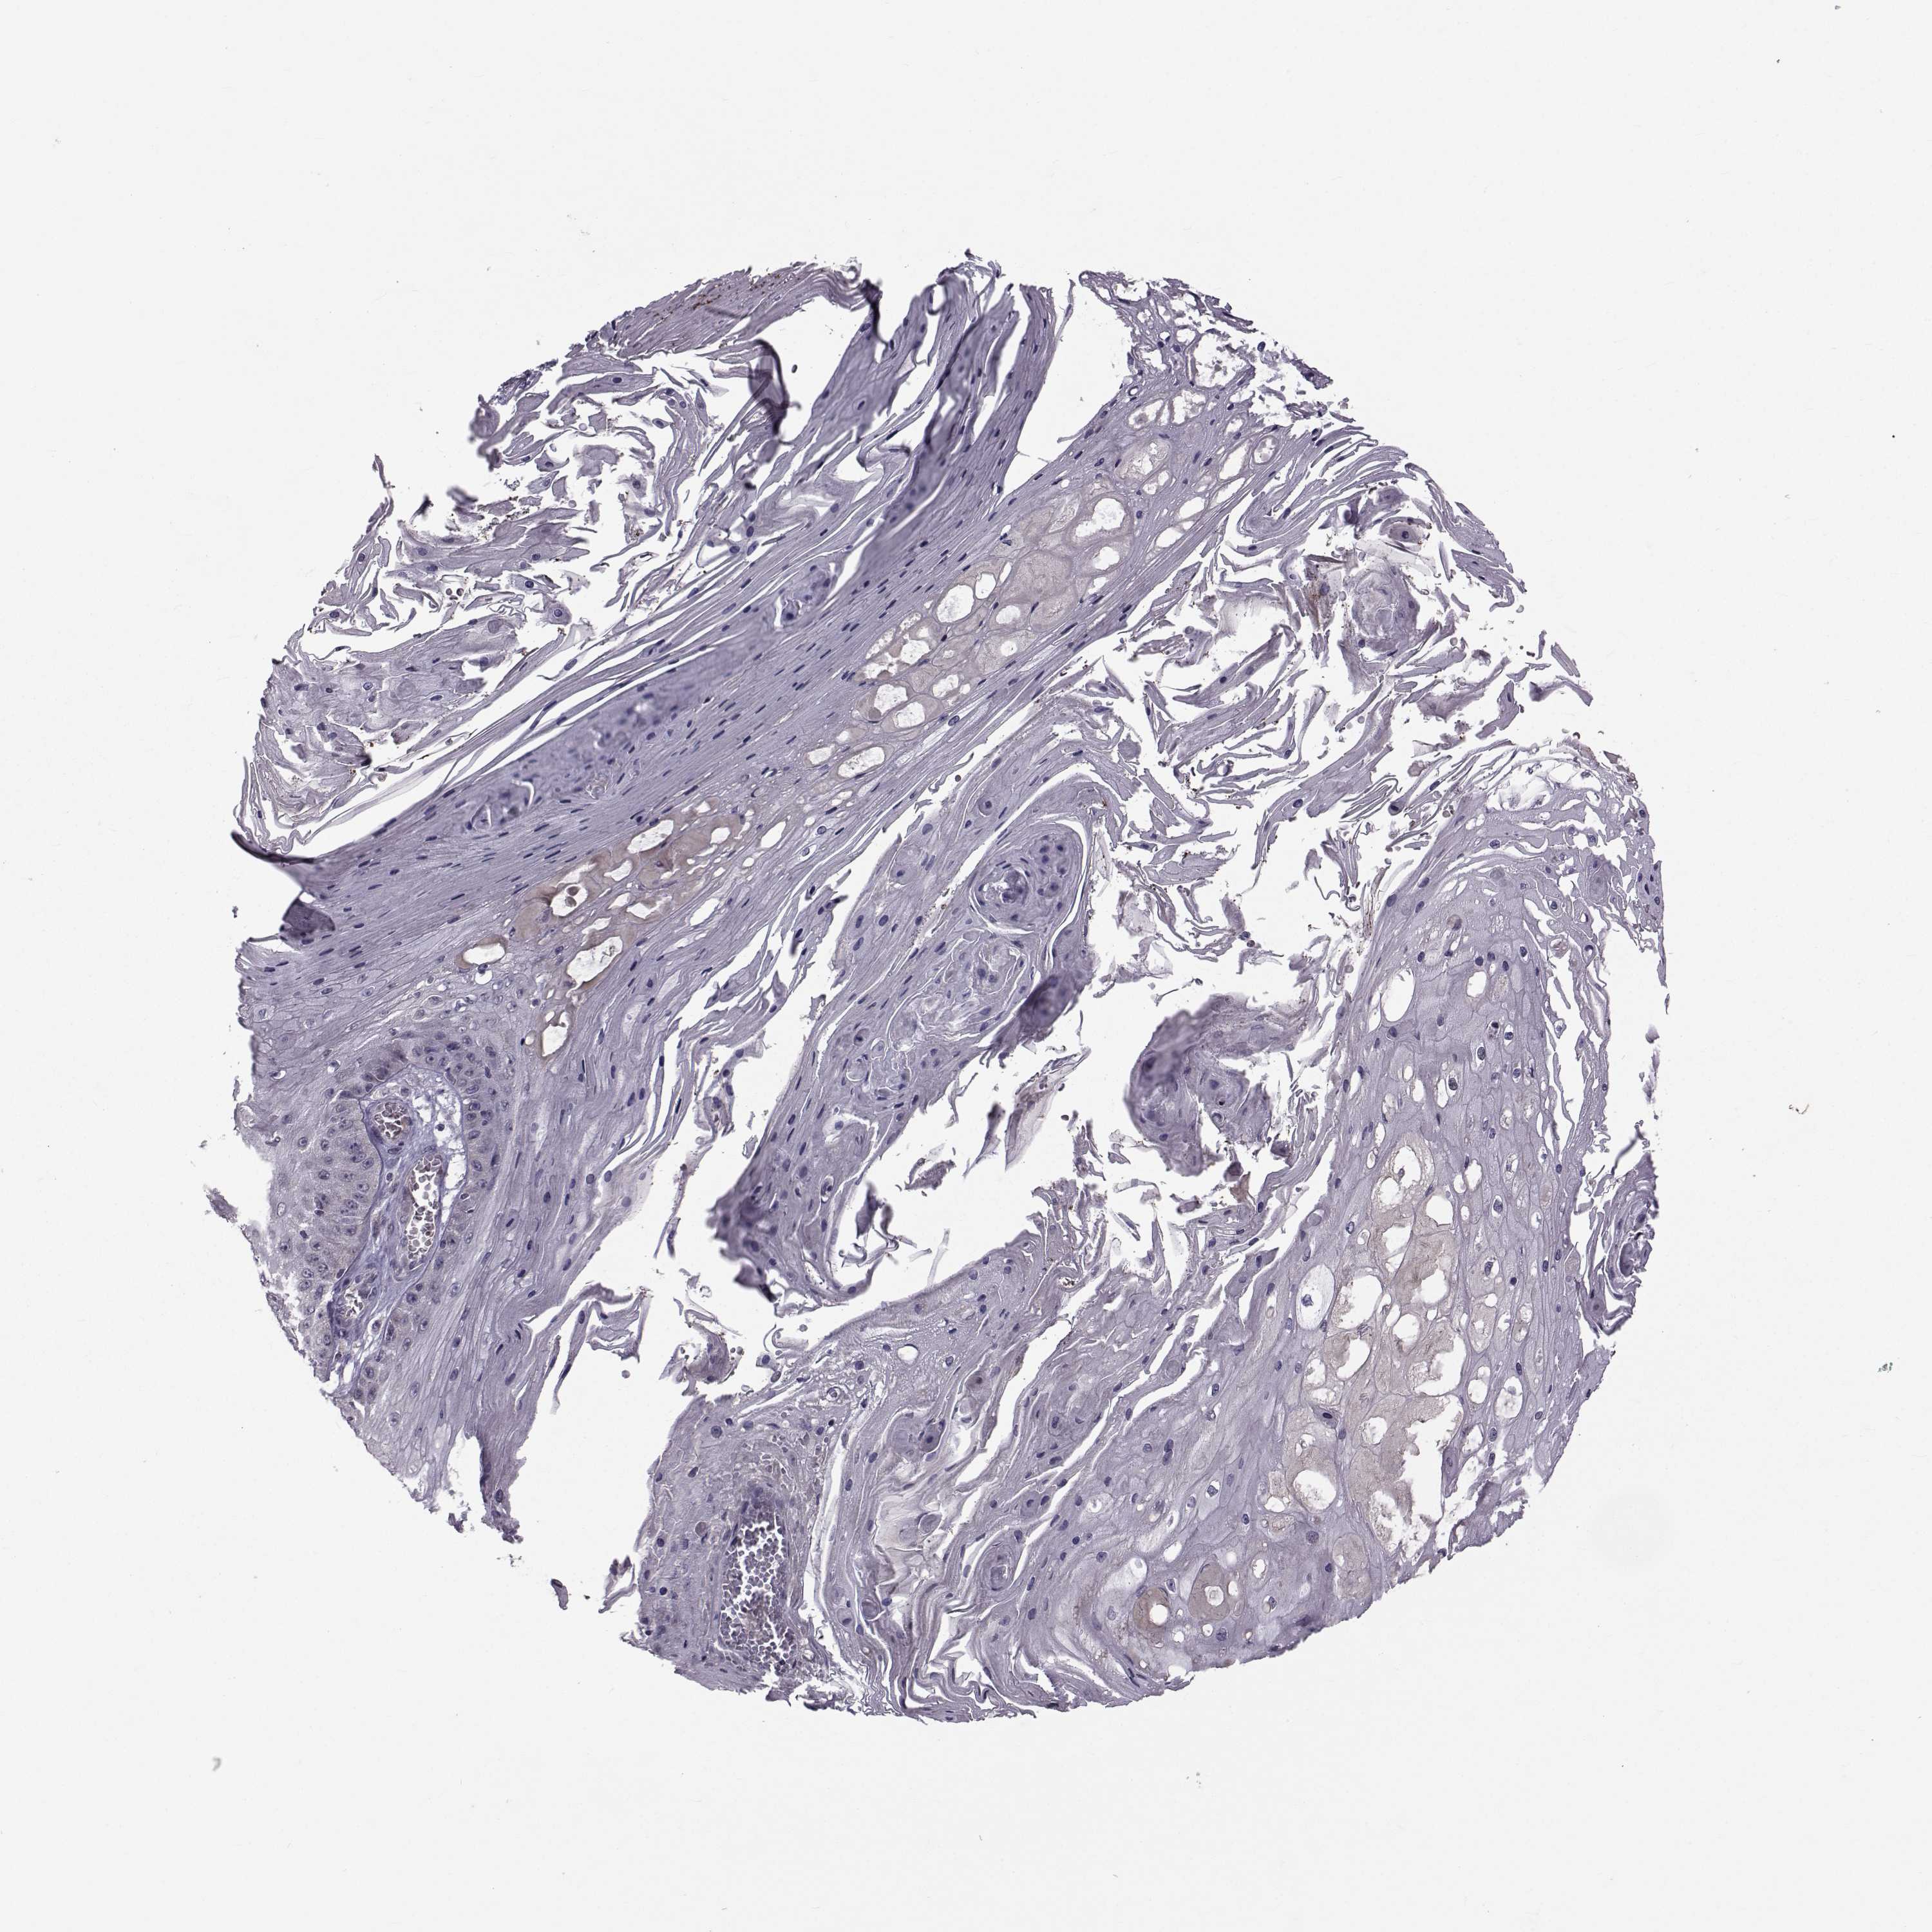

Basal cell and squamous cell cancer

SKIN CANCER - Protein expressioni

A mouse-over function shows sample information and annotation data. Click on an image to view it in a full screen mode. Samples can be filtered based on level of antibody staining by selecting one or several of the following categories: high, medium, low and not detected. The assay and annotation is described here.

Antibody stainingi

Antibody staining in the annotated cell types in the current human tissue is reported as not detected, low, medium, or high, based on conventional immunohistochemistry profiling in selected tissues. This score is based on the combination of the staining intensity and fraction of stained cells.

Each image is clickable and will lead to virtual microscopy that enables deeper exploration of all samples and also displays staining intensity scores, fraction scores and subcellular localization as well as patient and tissue information for each sample.

Antibody HPA044393

Antibody HPA053673

Antibody CAB009818

Staining

High

Medium

Low

Not detected

Intensity

Strong

Moderate

Weak

Negative

Quantity

>75%

75%-25%

<25%

None

Location

Nuclear

Cytoplasmic/membranous

Cytoplasmic/membranous,nuclear

Squamous cell carcinoma, NOS

Basal cell carcinoma